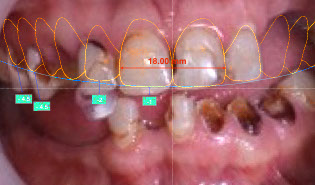

Brener Clinic takes a series of high-quality digital photos and videos to analyse thoroughly your facial and oral proportions and movement. This data helps us determine the relationship between your smile line, teeth, gums and lips, and how they move together with your individual personality. This analysis allows us to digitally design your smile using DSD technology and plan the treatment.

iv) Clinical analysis and digital design of new smile